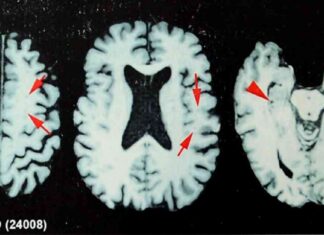

Study Suggests One-Third of Ex-NFL Players Believe They Have CTE A recent study has shed light on the prevalence of chronic traumatic encephalopathy (CTE) among former professional football players. The research, published in the journal...